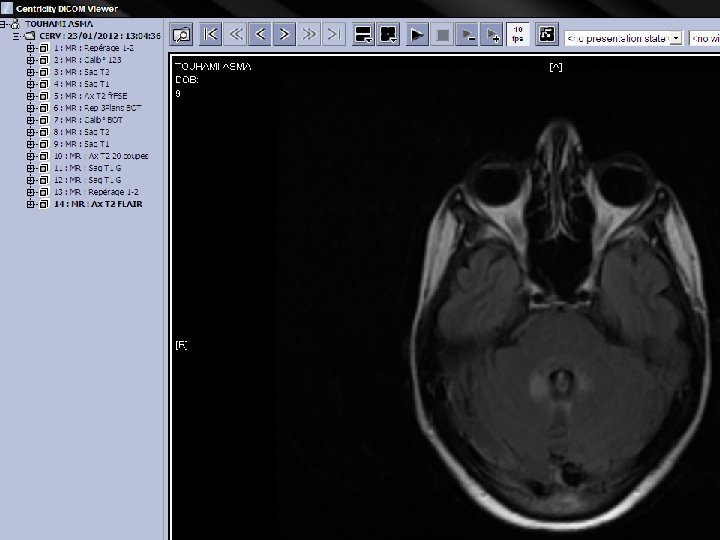

q IRM: d’hpersignaux sub blanche. Sur les séquences pondérées en T 2, les images ne sont pas spécifiques mais leur répartition et leur aspect évoquent des lésions de démyélinisation. Péri ventriculaire, en sub blanche profonde. Arrondies ou ovalaire, taille variable: qlq mm à qlq cm. Evocatrices en péri ventriculaire, sus tensorielle, médullaire.

Séquence T 1 après injection de Gadolinium st informative, les lésions rehaussées/Gado st évolutives. L’hyper signal induit /Gado est svt annulaire en périphérie de la lésion.

SEP Dissémination dans l’espace IRM: lésions multiples et sans R/ avec la symptomatologie apportée. La présence d’au moins 4 lésions dont 1 péri ventriculaire est significative. Dissémination dans le temps Aspect différent de lésions mais surtout le rehaussement de certaines d’entre elles témoignant de lésions d’ages différents.

Figure 1. IRM en séquence T 1 : « trous noirs » dans la substance blanche

Figure 2. IRM en séquence FLAIR : hypersignaux à prédominance périventriculaire.

Figure 3. IRM en séquence T 1 avec injection de gadolinium : lésions périventriculaires.

Figure 4. IRM en séquence T 2 : hypersignaux à prédominance périventriculaire.